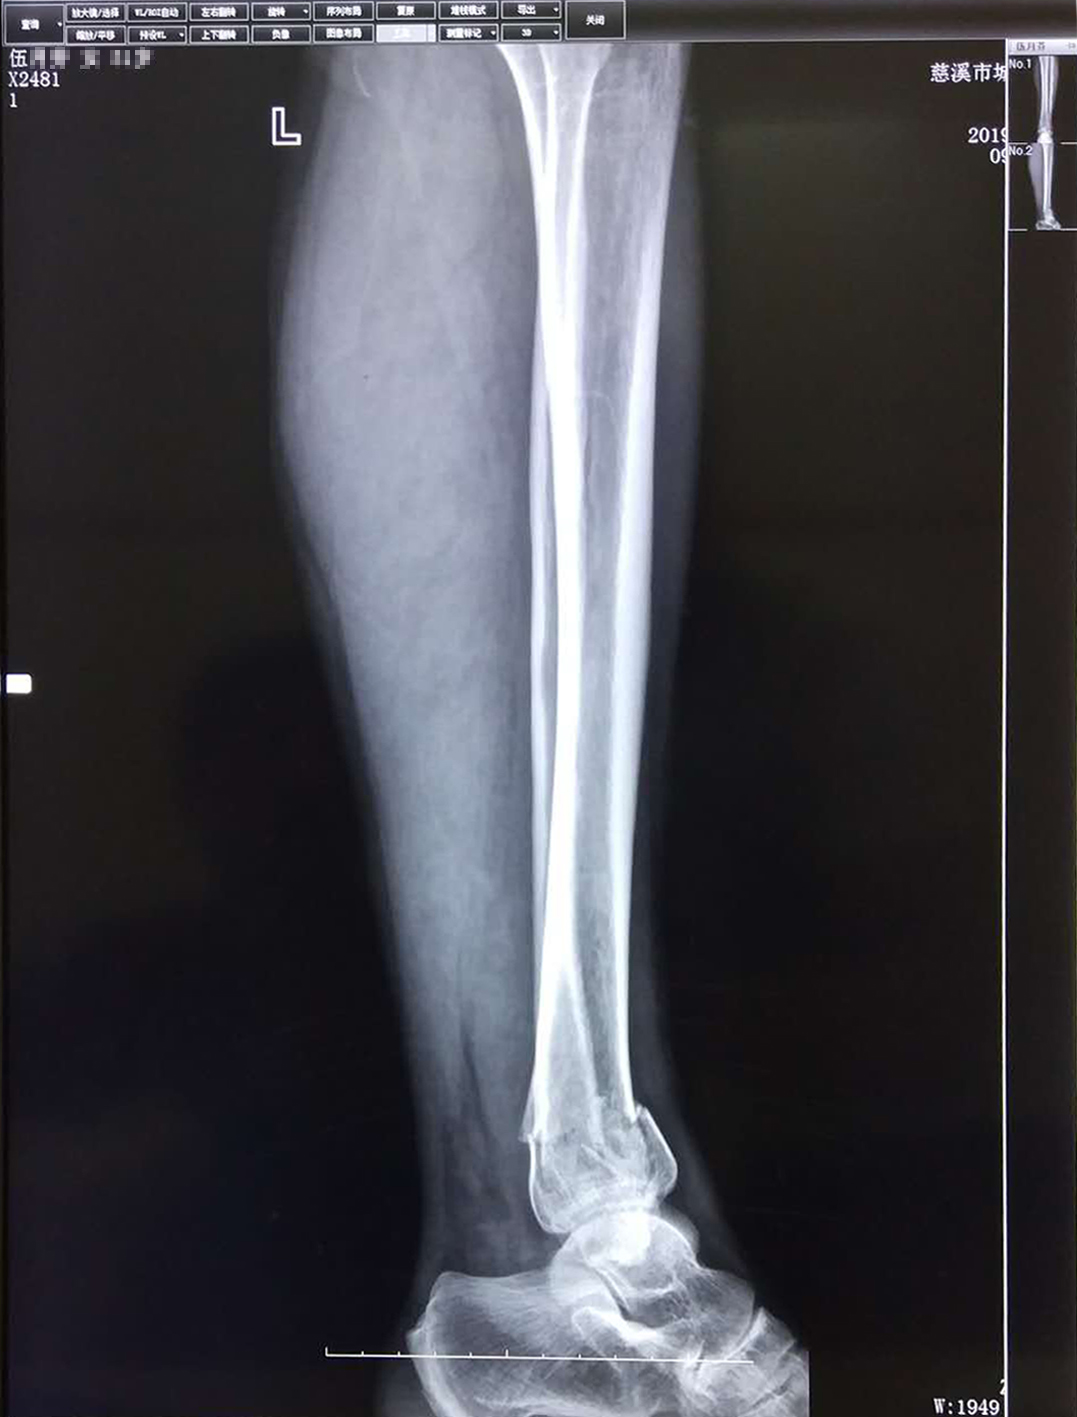

孙培权医师杏林妙手 成功使下腿双骨折错位患者康复_伍女士

图片尺寸1077x1417